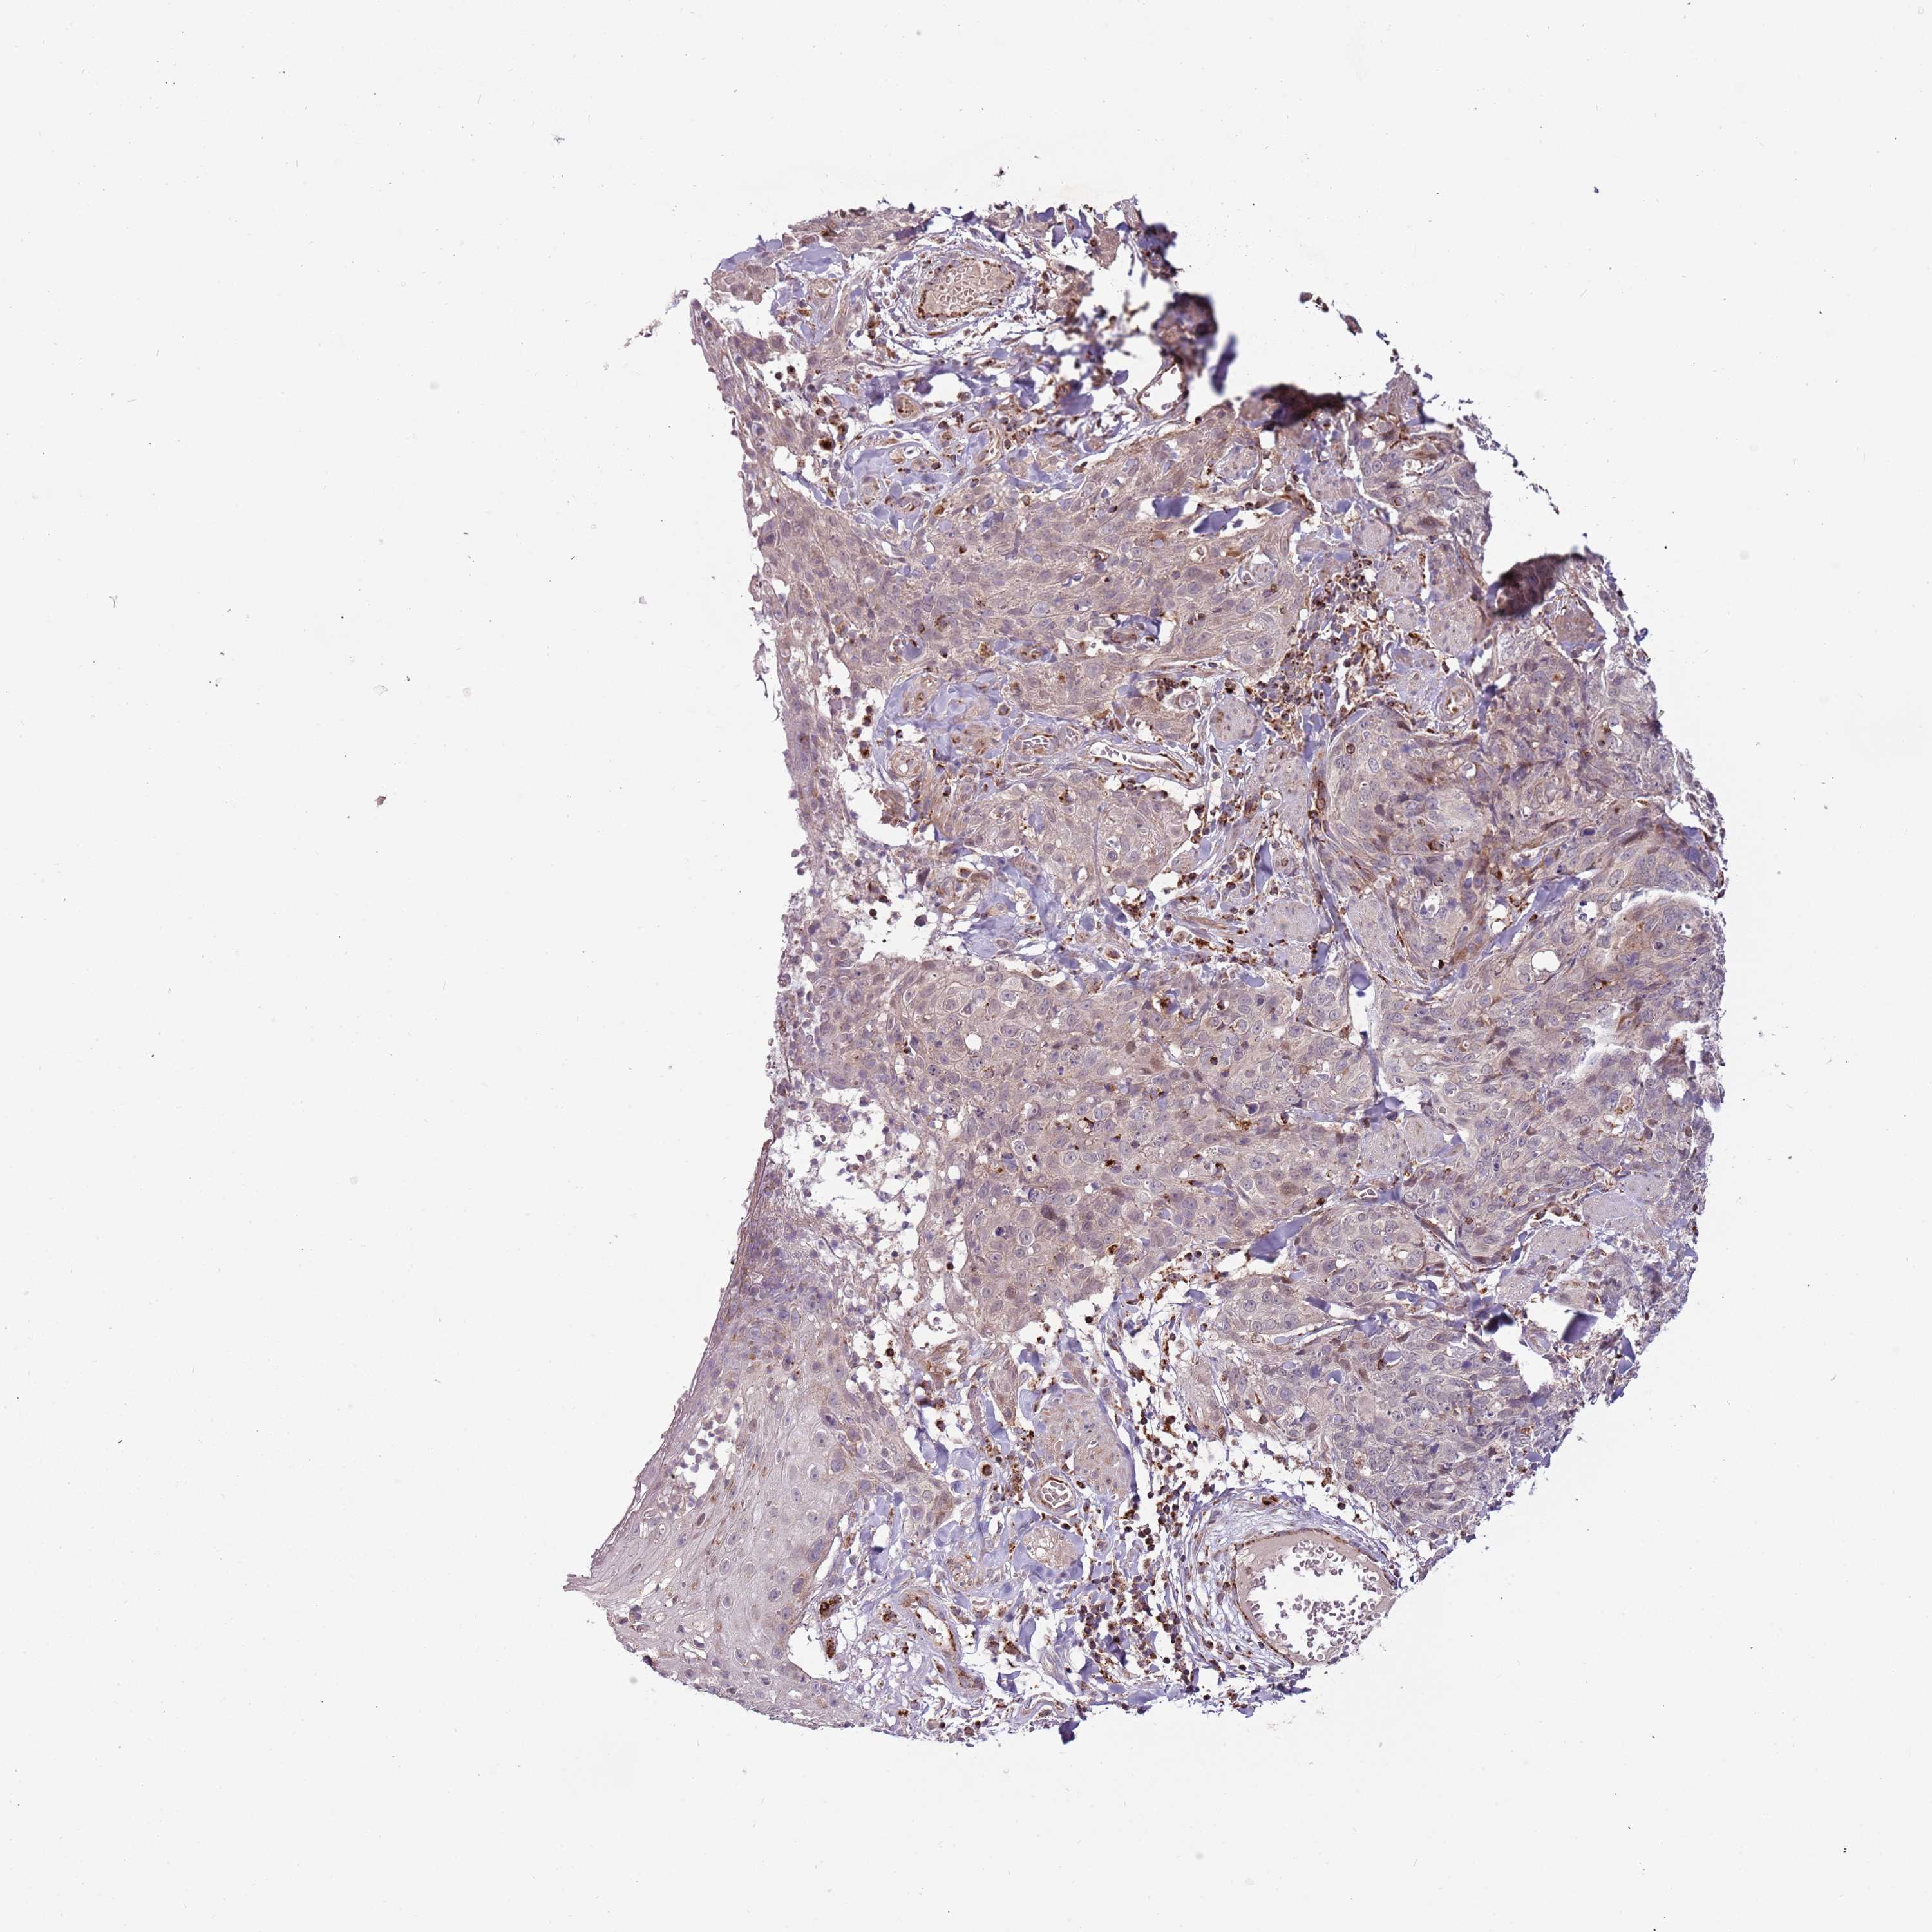

SKIN CANCER - Protein expressioni

A mouse-over function shows sample information and annotation data. Click on an image to view it in a full screen mode. Samples can be filtered based on level of antibody staining by selecting one or several of the following categories: high, medium, low and not detected. The assay and annotation is described here.

Antibody stainingi

Antibody staining in the annotated cell types in the current human tissue is reported as not detected, low, medium, or high, based on conventional immunohistochemistry profiling in selected tissues. This score is based on the combination of the staining intensity and fraction of stained cells.

Each image is clickable and will lead to virtual microscopy that enables deeper exploration of all samples and also displays staining intensity scores, fraction scores and subcellular localization as well as patient and tissue information for each sample.

Antibody HPA040474

Basal cell carcinoma

Squamous cell carcinoma, NOS

Squamous cell carcinoma, metastatic, NOS